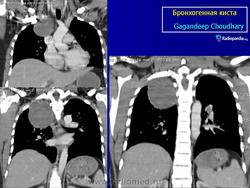

Рентгенологическая картина. При кисте, заполненной жидкостью, обнаруживается округлое или овальное затенение с четкими контурами. Контуры затенения могут изменяться в зависимости от фазы дыхания. При бронхогенной кисте, заполненной воздухом, видна правильной формы полость с чрезвычайно четким контуром, на фоне которой легочный рисунок обычно ослаблен. Более отчетливо просветление прослеживается на томограммах. Небольшой уровень жидкости на дне наблюдается не всегда, однако этот симптом, весьма важен с точки зрения дифференциальной диагностики истинных бронхогенных кист, продуцирующих секрет, от воздушных полостей другого происхождения (булл). Бронхография. Контраст не всегда попадает в полость из-за чрезвычайно узкого сообщения последней с просветом бронхиального дерева.

ID: 22985 Bronchogenic cyst Dr Mostafa Mahmoud El Feki - 10 May 2013 Features consistent of bronchogenic cyst. Differential considerations in...

ID: 10946 Bronchogenic cyst Dr Gagandeep Choudhary - 3 Oct 2010 CT through the chest demonstrates a large fluid density cystic structure...